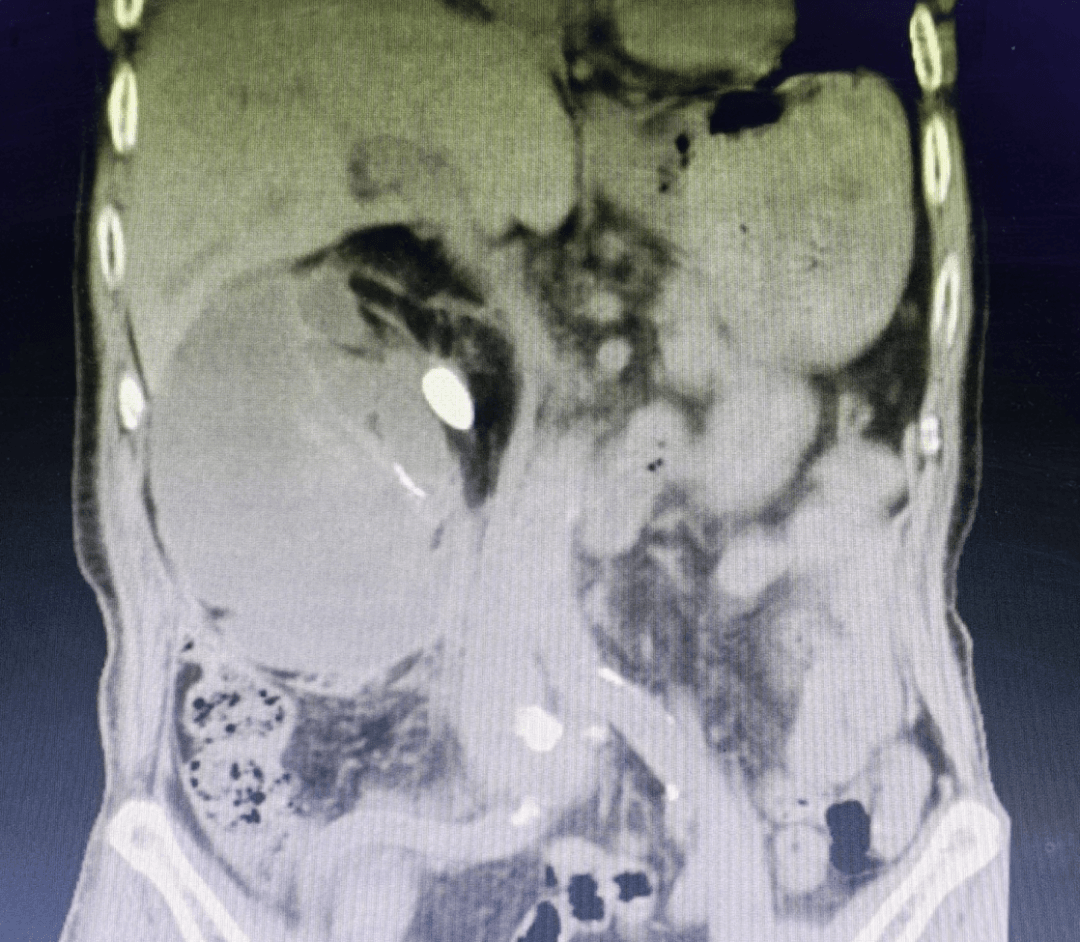

入院时CT片

经初步检查发现杨爷爷肾结石多发且引起右肾重度积水并出血,肾功能严重损害,合并有胸腔大量积液、心脏病、贫血等基础疾病,麻醉和手术风险极高。患者希望“既要治病,又要保肾。”为帮助杨爷爷解除多年疾病困扰,泌尿外科学科带头人罗洪星带领专家团队联合麻醉科、呼吸内科、ICU、心内科等多学科专家经过反复讨论和分析,结合患者诉求,最终为杨爷爷制定了个性化治疗方案。